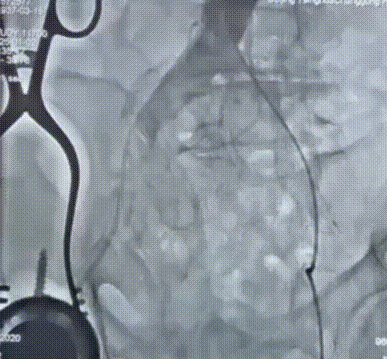

撤出大鞘,造影提示外周血管无出血、无夹层

血管入路造影检查